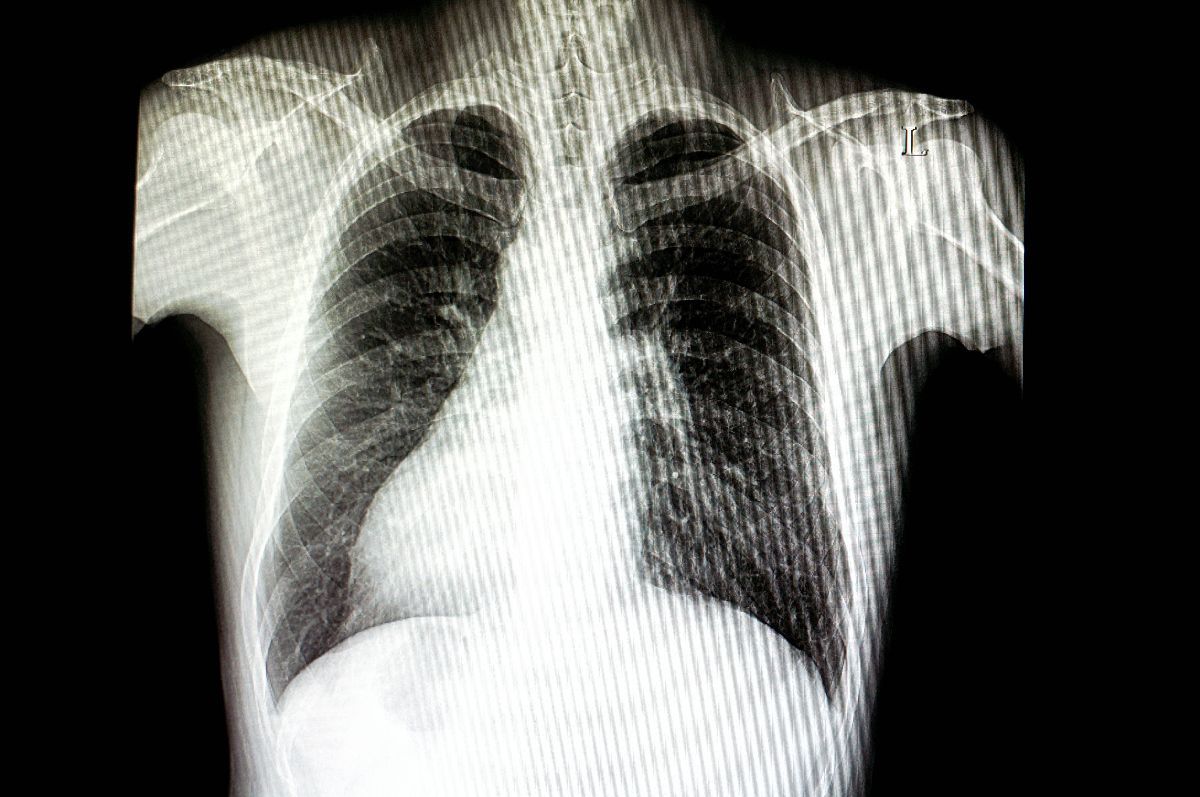

Foto 7/18 : Situs inversus, anomalia congenitală în cadrul căreia anumite organe sunt situate în partea opusă față de situația normală / Sursă foto: Imago Images